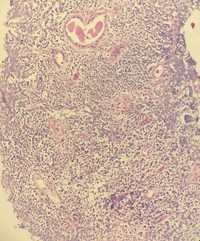

Renal biopsy involved by follicular lymphoma, low-power

Light microscopy, H&E: minimal intact renal parenchyma demonstrating tubular injury with interstitial lymphoid process